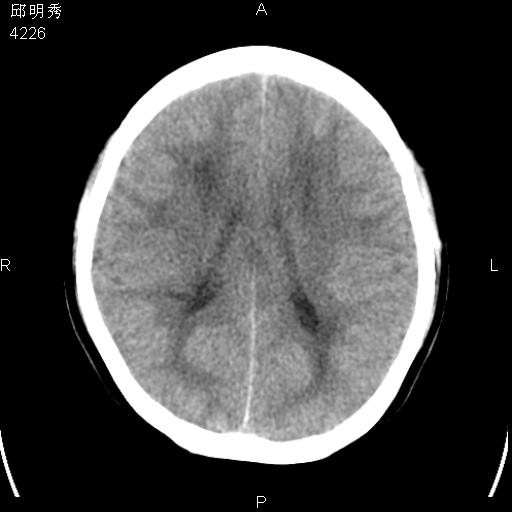

40f头晕十多天,右上肢麻木一天

脑白质变性或ms

脑白质脱髓鞘改变。

脑白质病;建议行mri检查。